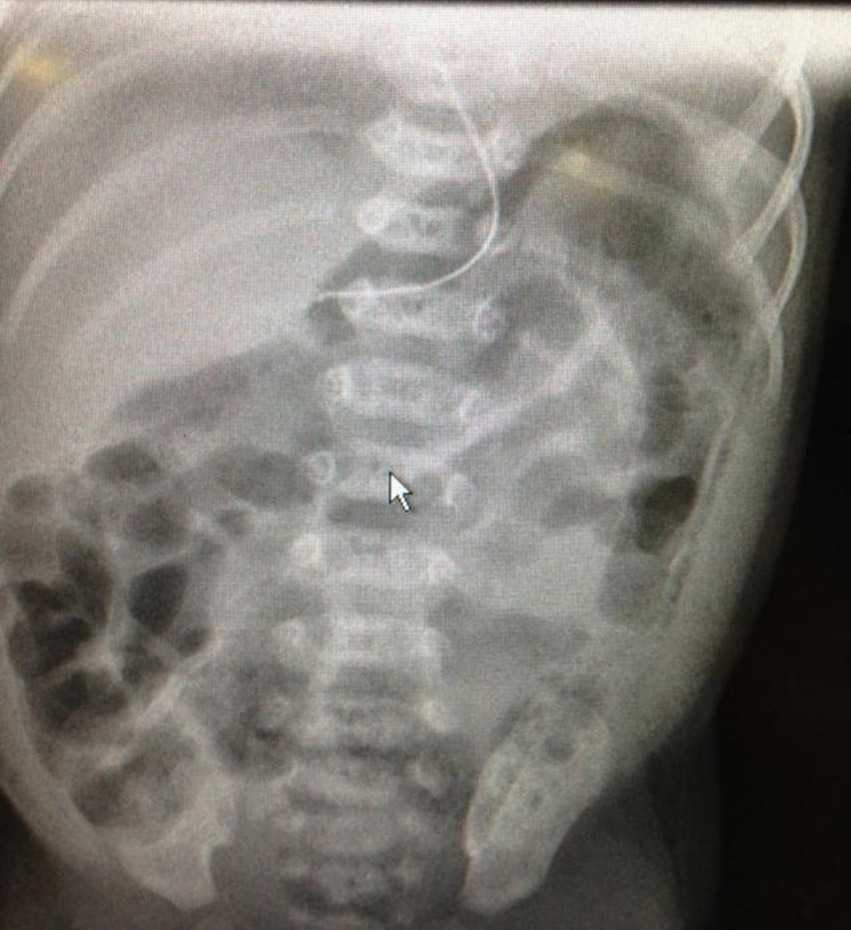

À l’examen clinique, vous notez : poids 3 300 g ; apyrexie ; FC : 150/mn ; FR : 40/mn ; SpO2 : 100 % en air ambiant ; geignement ; PC : 35,5 cm ; temps de recoloration cutanée (TRC) à 1 seconde ; abdomen ballonné, tendu, douloureux à la palpation ; absence de contracture abdominale ; auscultation cardio-pulmonaire normale ; fontanelle normotendue ; hypotonie généralisée.